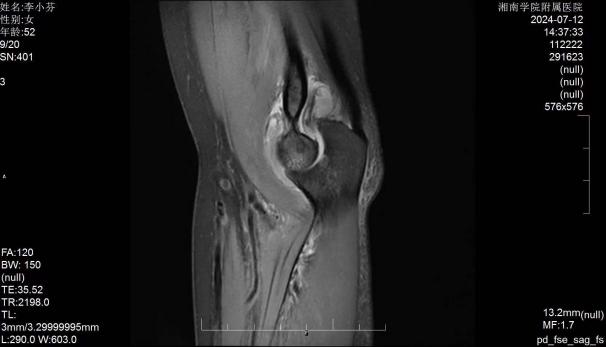

郴州市的李女士,因肘关节疼痛伴活动受限多年,辗转多家医院就诊,曾采用康复锻炼、封闭治疗、小针刀等多种方式进行治疗,均未能完全缓解。随着时间推移,李女士肘关节活动度受限逐步加重,屈、伸时疼痛,对日常生活造成很大困扰。听闻湘南学院附属医院骨二科李杨教授在关节微创治疗有丰富治疗经验,遂慕名而来。骨二科主任李杨教授经过详细的病史问询、物理查体、影像学检查,确诊李女士为左肘关节僵硬及肘关节滑膜炎性增生。住院后经过严密的术前分析讨论,最终决定采用微创技术为李女士实施关节镜下肘关节滑膜清理+关节松解术进行治疗。

术前影像学资料